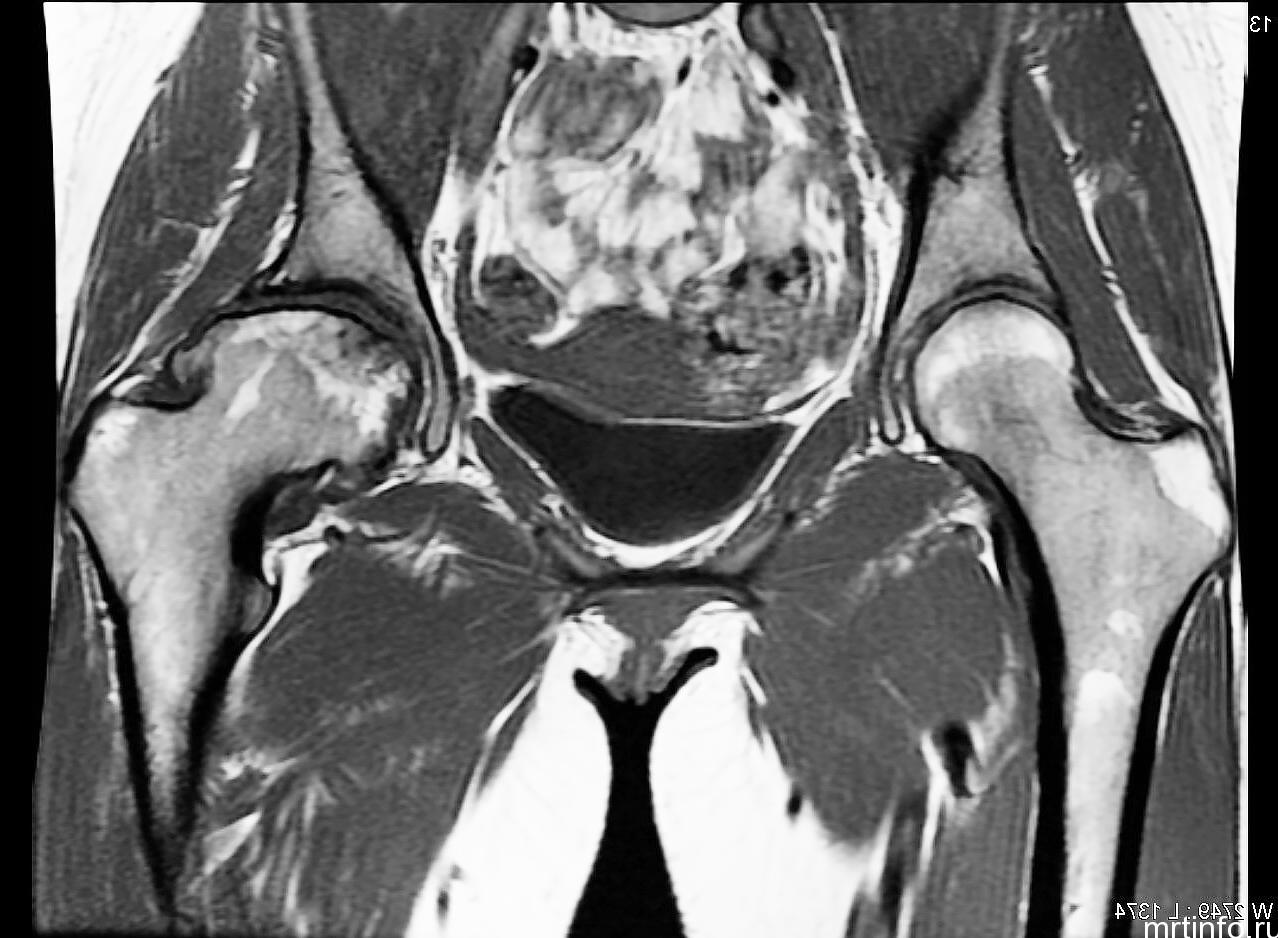

Тазобедренный сустав является самым крупным соединением организма и играет решающую роль в обеспечении прямохождения. Придавая ноге свободу движений во всех плоскостях, наряду с этим подвержен огромному количеству патологических воздействий. Любые нарушения в тазобедренном суставе проявляют себя в виде болевого синдрома.

Болезненным изменениям могут подвергаться все его составные части: кости, мышцы, окружающие точки соединения бедра и таза, суставные хрящи, сухожилия, сосуды и нервы, оплетающие сустав.

В отношении исследования всех вышеперечисленных структур, вне конкуренции многие другие методики оставляет магнитно-резонансная томография.

Магнитно-резонансная томография тазобедренного сустава — самый распространенный способ диагностирования патологий, расположенных в данной области. Именно этот метод позволяет получить полную картину состояния сустава, а также прилегающих мягких тканей, сосудов, сухожилий и связок. Только МРТ имеет возможность рассмотреть патологии на самых ранних стадиях, когда они еще не заметны для прочих видов исследования, и заблаговременно начать лечение, предотвращая болезнь. В сравнении с полноценным такое лечение обойдется недорого и, что важнее, не так рискованно для здоровья.

МРТ позволяет получить подробное трехмерное изображение исследуемой области — подобной точностью не отличается ни один прочий способ. МРТ является безопасным диагностическим методом, так как не оказывает на организм лучевой нагрузки — благодаря этому проводить обследование можно так часто, как это необходимо. МРТ не требует реабилитации, неинвазивна и разрешена даже беременным женщинам во второй половине беременности. Единственным недостатком метода можно считать разве что то, сколько стоит МР-томография: этот метод определенно не является бюджетным.

Магнитно-резонансная томография — единственный способ выявить метастатические изменения костной структуры в тот период, когда рентген еще не способен их рассмотреть. Только одну эту способность можно считать незаменимой и полностью покрывающей собой всю стоимость МРТ тазобедренного сустава. МРТ назначается при болях в данной области и травмах бедра, с помощью МР-томографии уточняются результаты других диагностических процедур.

Возможность при необходимости выделить сосудистую сеть и отдельные сосуды, нервные стволы на МР-сканах незаменима при планировании этапов хирургического лечения (например, МРТ воспаленных тканей в области эндопротеза тазобедренного сустава при вопросе о ревизии). Чаще всего данную методику в отношении тазобедренного сустава применяют в травматологии и хирургии, а также онкологии.

- аваскулярный (асептический) некроз головки бедра